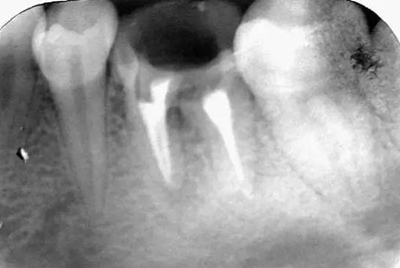

初尖銼,根測儀測量長度后拍照

初尖銼X光片:現(xiàn)在根測儀的準(zhǔn)確性的卻非常之高。

根充后: